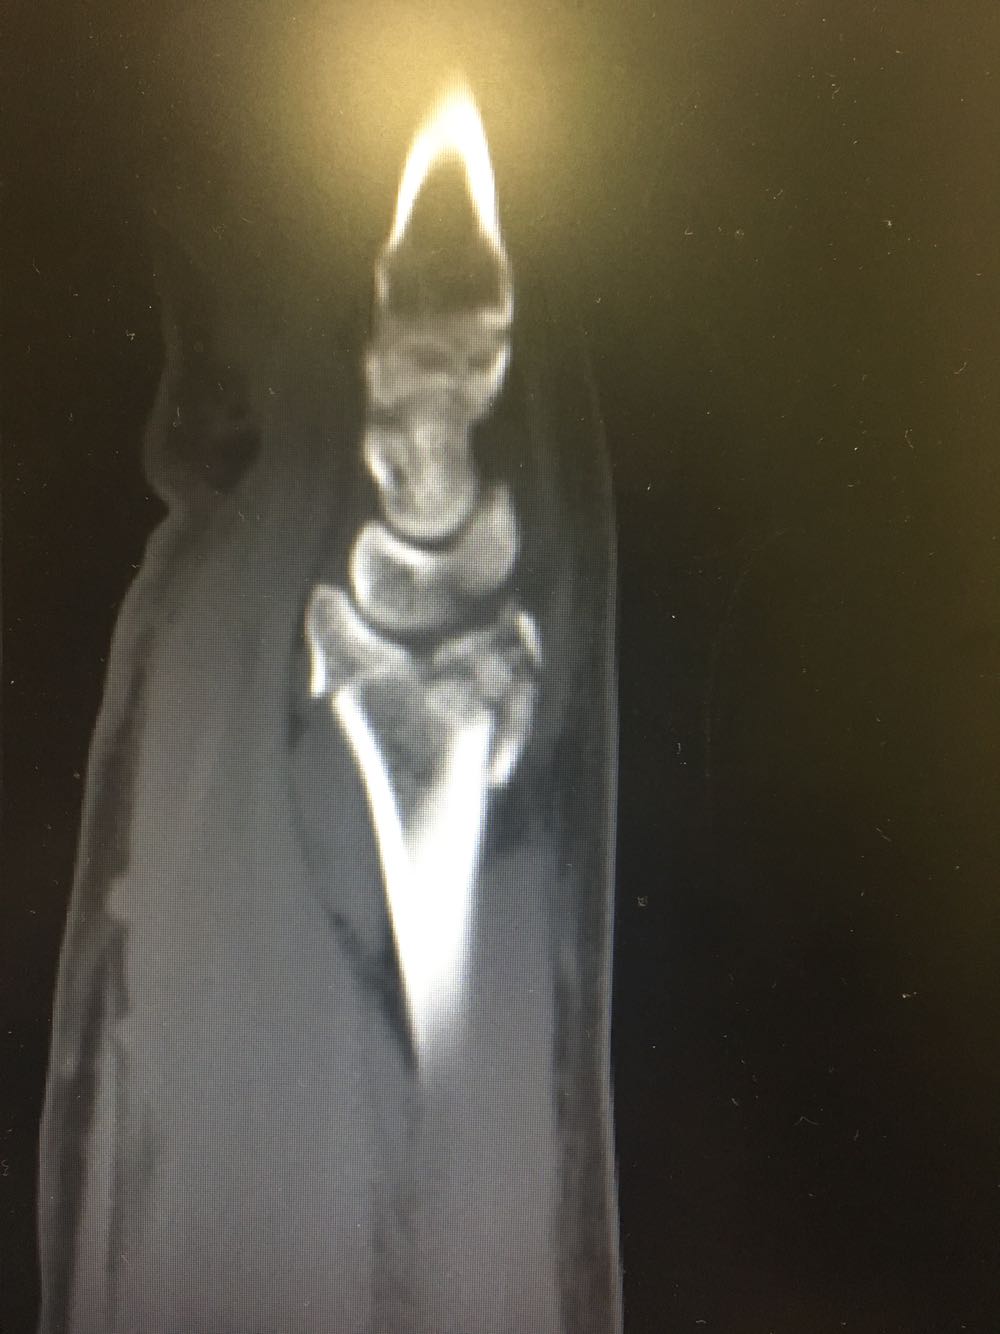

右尺桡骨双骨折

患者,男性,52岁 主诉:摔倒后右腕关节活动受限2天 现病史:患者于2天前于不慎,身体向右摔倒,右手掌着地后突感右侧腕部剧烈疼痛,后出现肿胀伴活动障碍,否认头晕头痛、恶心呕吐等不适,未见淤斑淤点,遂至我院就诊,查X片示:右侧桡骨远端及齿骨茎突骨折,现为进一步诊治收治入院,发病以来,神清,精神可,胃纳夜眠可,二便无殊,体重无明显变化。

查体:右手腕部压痛明显,伴活动受限,其余部位压痛不明显,患侧手指感觉及运动正常。 辅检:腕部CT

诊断:尺桡骨远端骨折(右侧) 治疗:完善术前检查后手术内固定